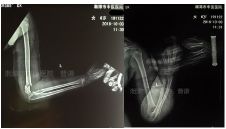

复位固定后拍片情况如下: